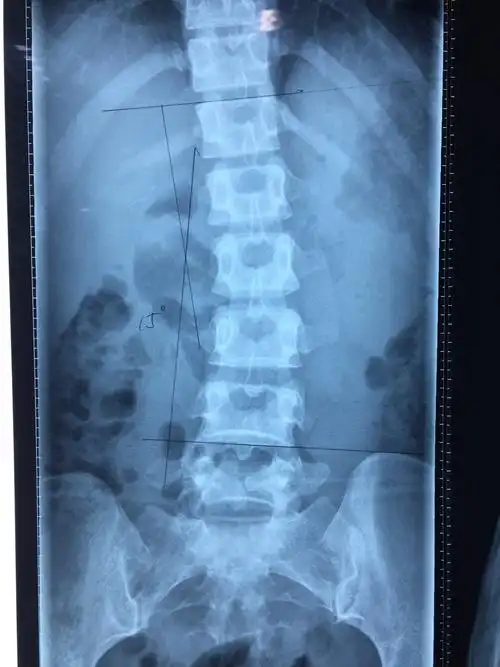

midlf手术治疗腰椎管狭窄症伴有腰椎退变性侧弯畸形

腰椎间盘竟引起脊椎侧弯,该怎么治!

腰椎侧弯畸形怎么办? - 好大夫在线